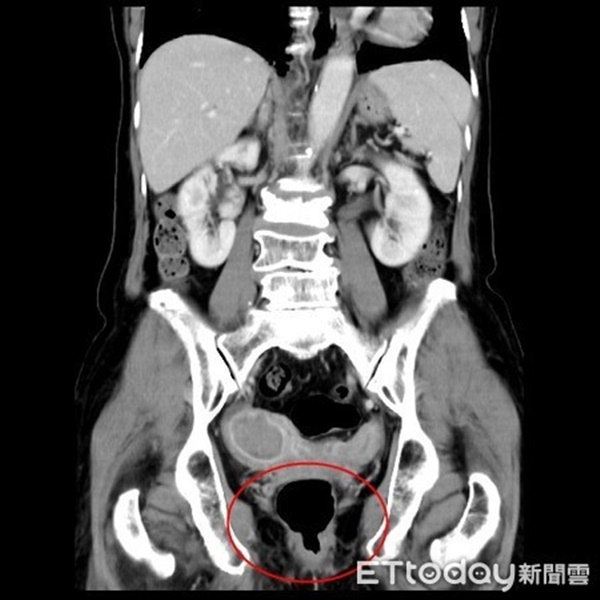

Bác sĩ Lê cho rằng đây là một dấu hiệu bất thường ở một người phụ nữ 74 tuổi nên đã cho bà đi siêu âm tử cung, kết quả cho thấy bà có "tử cung hai sừng", đây là một dạng dị tật bẩm sinh. Sở dĩ gọi là tử cung hai sừng vì hai bên tử cung có phần nhô lên giống như sừng, trong lòng tử cung có một vách ngăn.

Ngoài ra, các bác sĩ còn tìm thấy 1 khối u nghi ngờ trong buồng tử cung bên phải, theo thăm khám bác sĩ xác định đây là khối u ung thư nội mạc tử cung. Như vậy, dấu hiệu chảy máu âm đạo của bà Hoàng không phải do kinh nguyệt mà là do 2 chứng bệnh này.